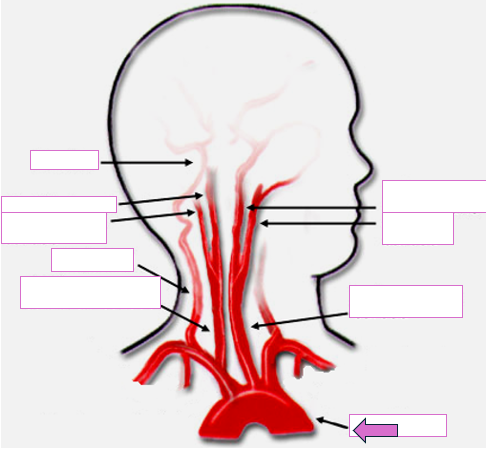

Based on the indicated area, identify this vessel

Basilar

Right internal carotid

Right external carotid

Vertebral

Right common carotid

Left internal carotid

Left external carotid

Left common carotid

Aortic arch